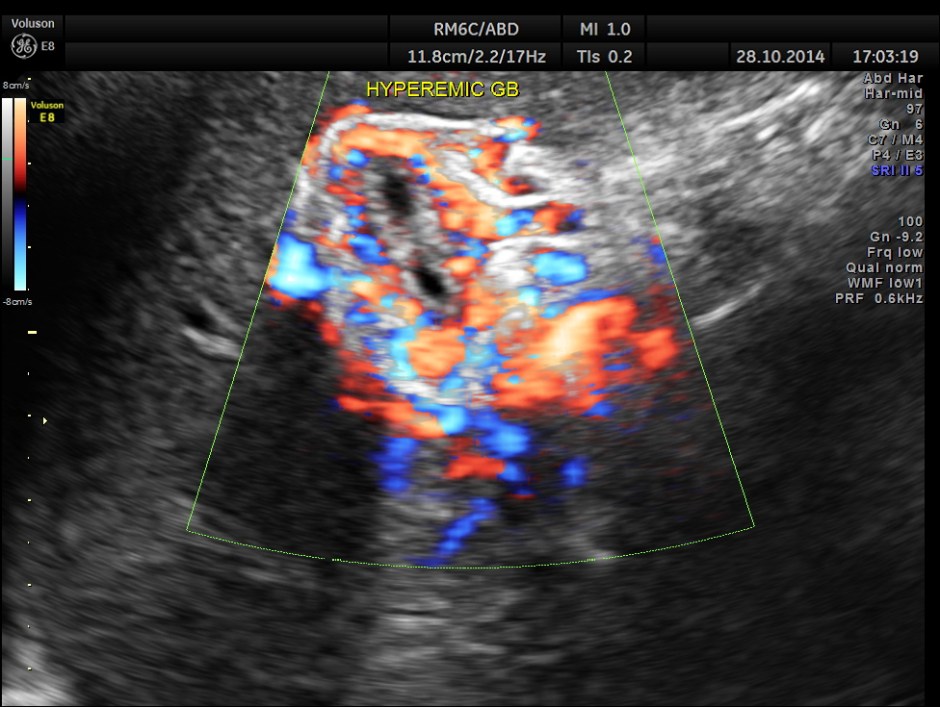

Hypo echoic linear spaces are seen around the gallbladder.

Colour flow imaging of the same